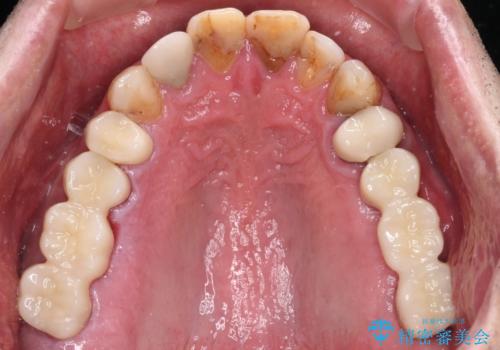

抜歯が必要な左右の奥歯 ブリッジとインプラントによる奥歯の補綴治療

- 咬んだときに奥歯に痛みを感じるとのことで来院された患者様です。

診査の結果、左側は奥歯2本、右側は1本の抜歯が必要であることが分かりました。

左側は大臼歯2本と小臼歯1本が欠損しているため、インプラント2本を治療したブリッジ、右側は中間欠損であり、前後の歯も加療が必要であったためブリッジによる補綴治療を行うこととしました。